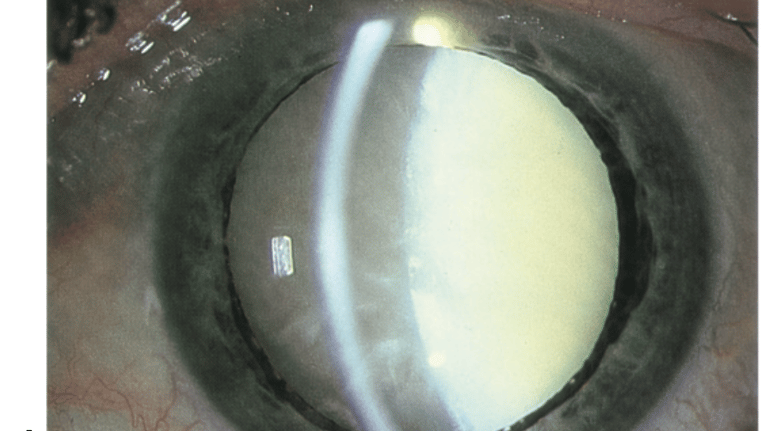

Nesta seção, explicamos as doenças oculares mais prevalentes de forma clara e acessível. Nosso objetivo é ajudar você a entender as causas, sintomas e tratamentos de condições como catarata, glaucoma, degeneração macular e outras. Com informações simples e diretas, queremos que você se sinta informado e confiante para cuidar da sua saúde ocular. Caso tenha dúvidas, nossa equipe está à disposição para ajudar.